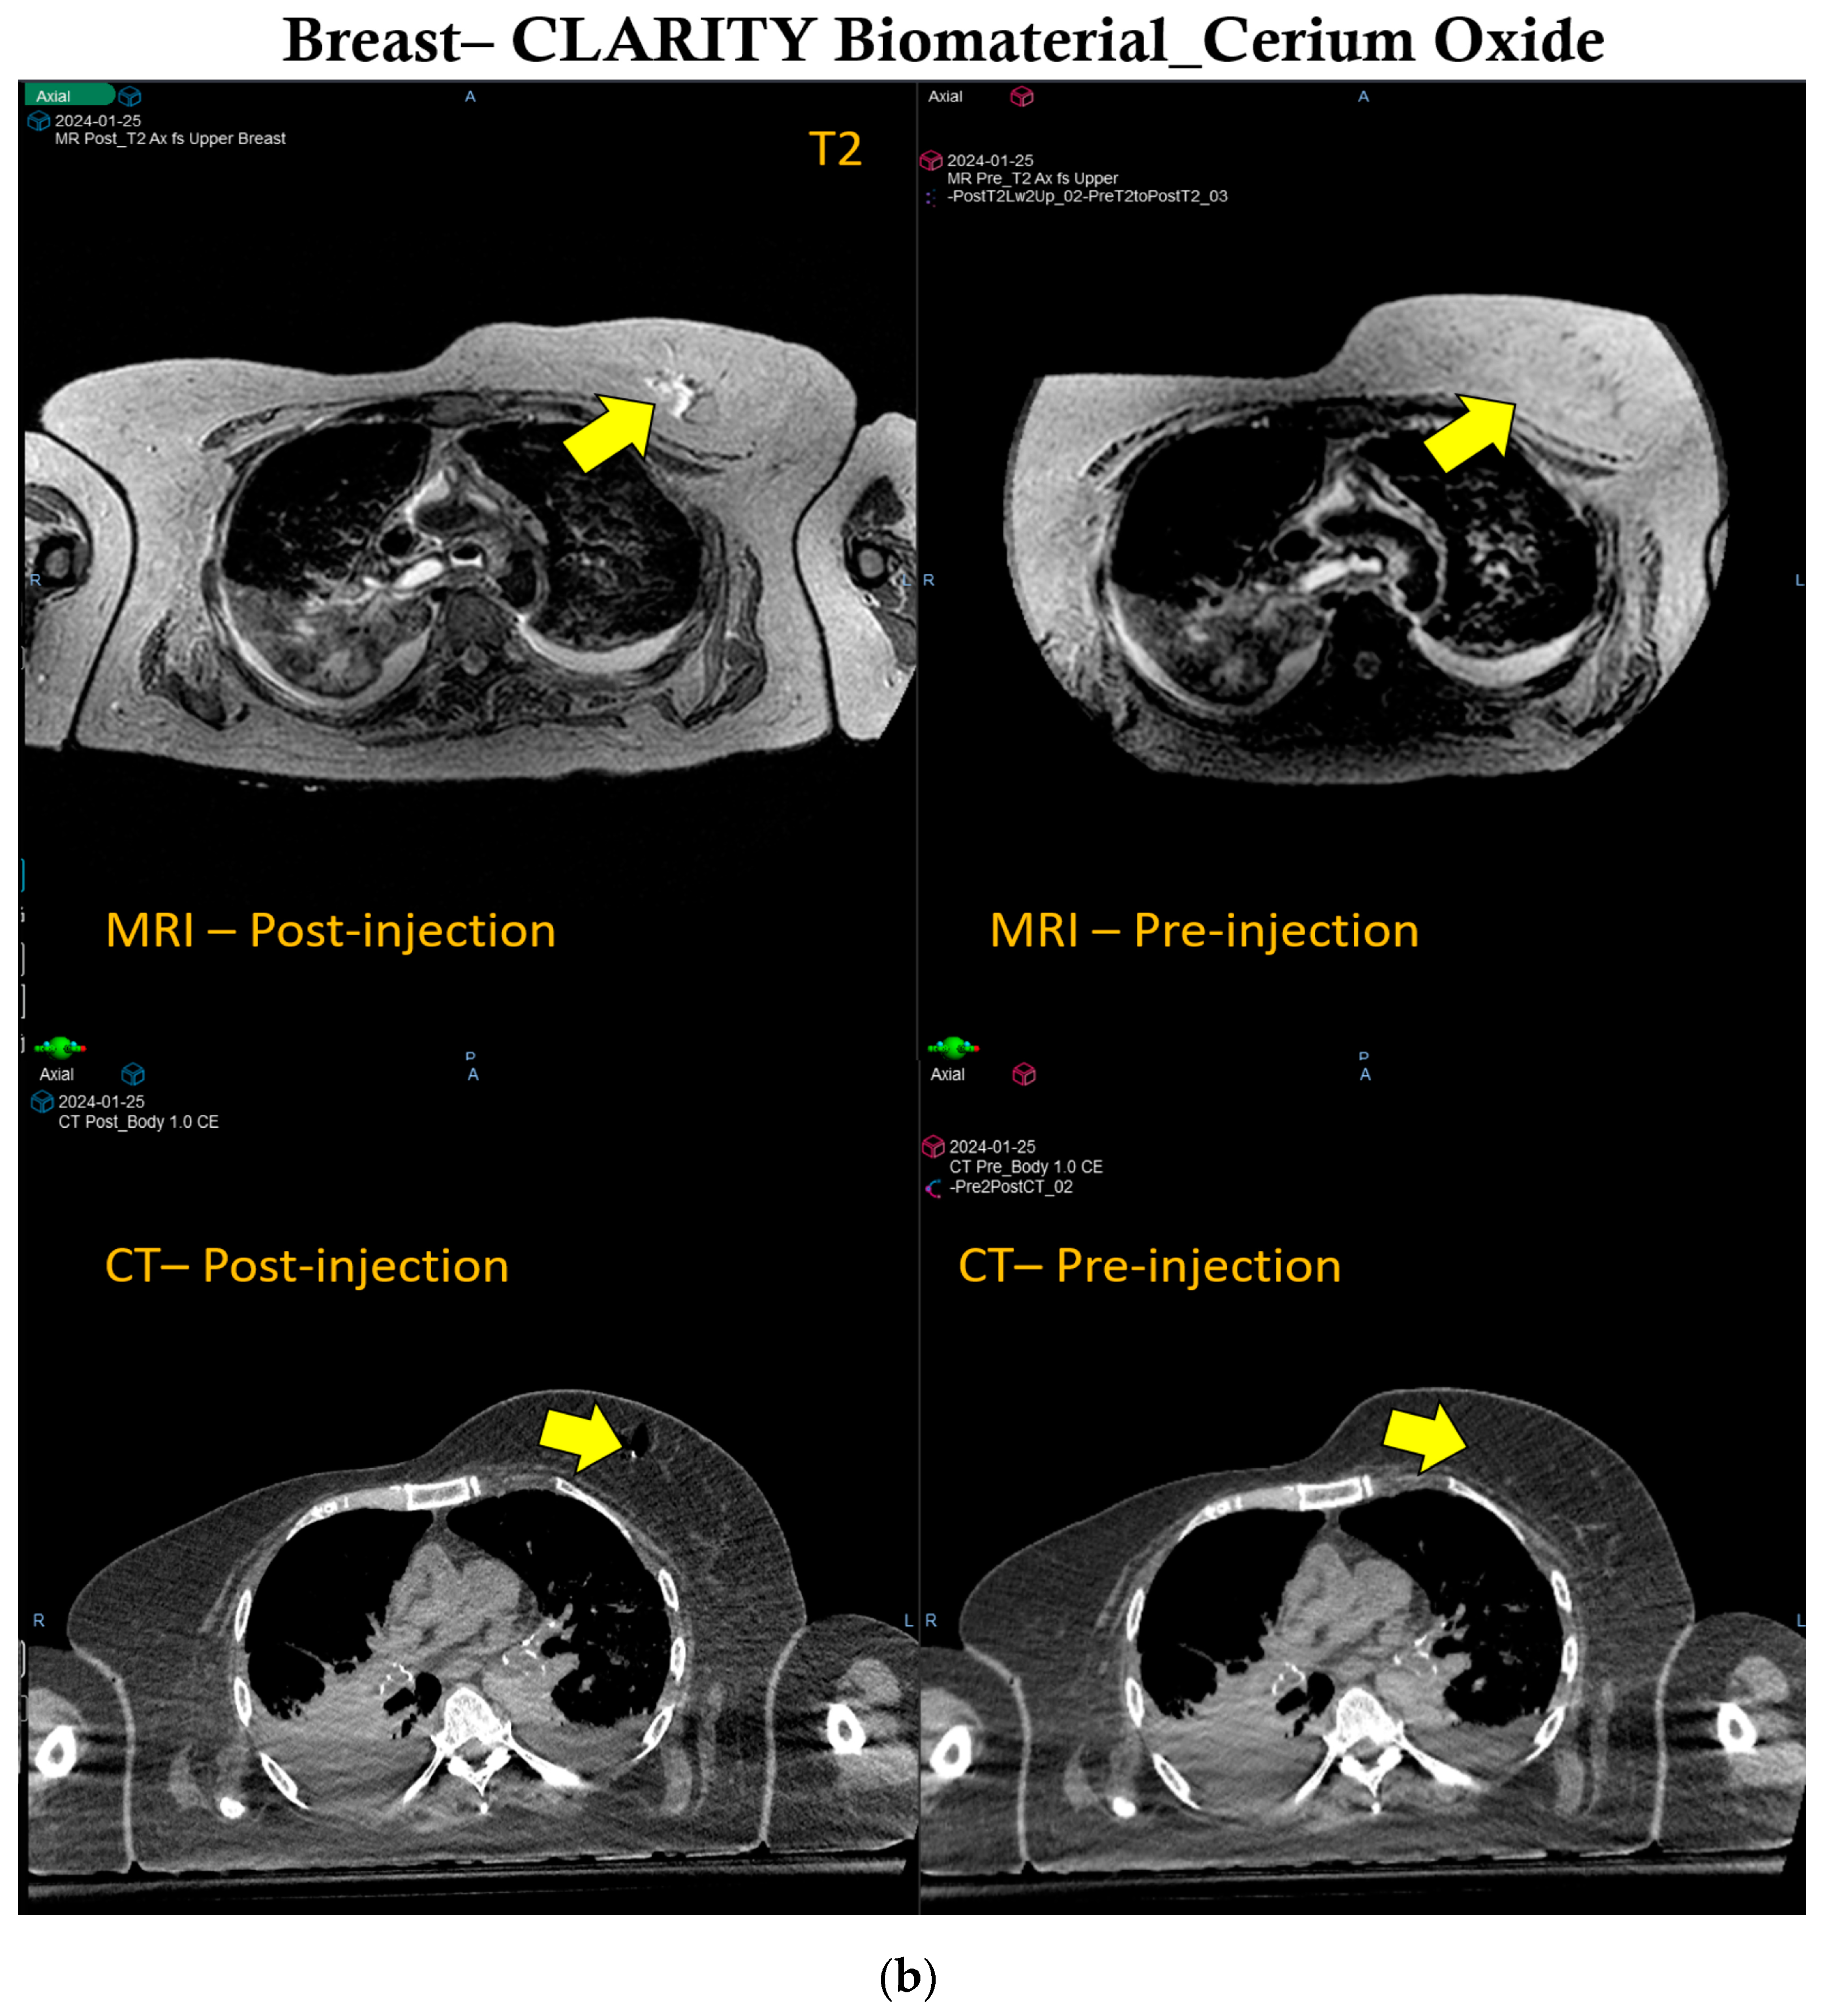

3.2. Image Guidance of CLARITY Biomaterial in Pancreatic Cancer